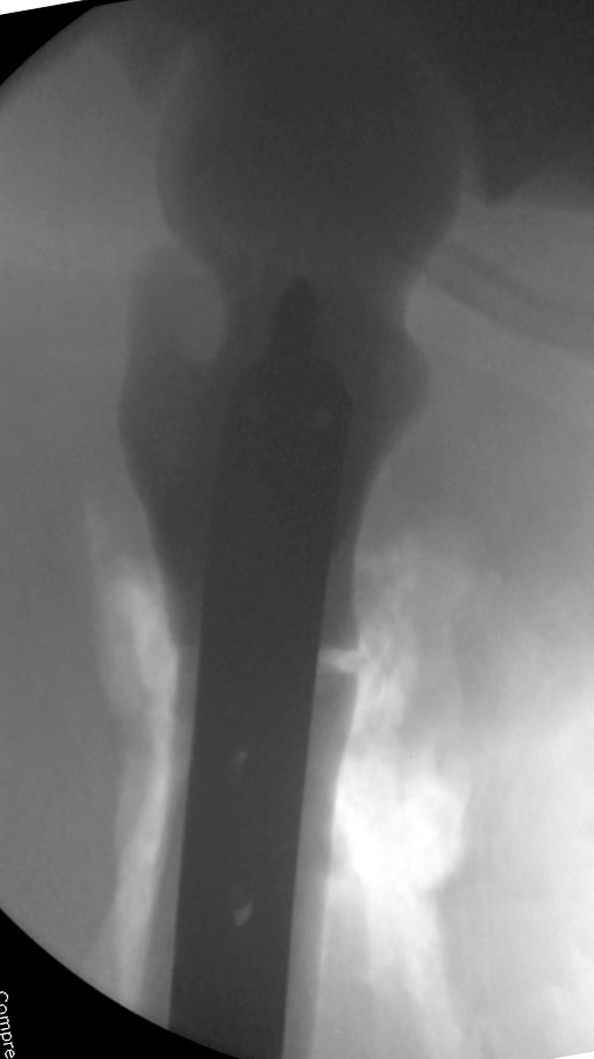

Что-то пациенту как-то не везет по жизни... Тоже самое - интрамедуллярный остеосинтез коротким штифтом для проксимального отдела бедра. Ранняя нагрузка сразу...

Наша тактика была бы - вертельный гамма стержень. Его длина 180 мм, должен поместиться до пластинки. Инструмент для формирования (не рассвреливания!) кнала, если он запаян, у нас есть.

Здесь у меня дополнительные снимки с большим разрешением и в разных режимах, а то те дигитал снимки совсем очень блеклые, может, эти изображени изменят выбор тактики

Не вызывает ли подозрение, что отсутствует медуллярный канал, как просверлить канал?

После неудачной попытки скелетного вытяжения в первом мед.учреждении, после осмотра снимков и изучения истории, поставили диагноз “Остеопетроз” или мраморная болезнь, редкая наследственная костная паталогия, где имеется нарушение формации остеокластов.

Конечно, было бы идеальным применение интрамедуллярного остеосинтеза, но учитывая прежний собственный опыт (лечил перелом бедра) и

публикации, предупреждающие о трудностях при обработке кости (иногда из-за неподготовленности инструментария результатом была неадекватная фиксация перелома, или перенос операции из-за фактора усталости оперирующего персонала), решили применить пластину (и в этом же случае был выбран Synthes plate, так что представитель за два дня